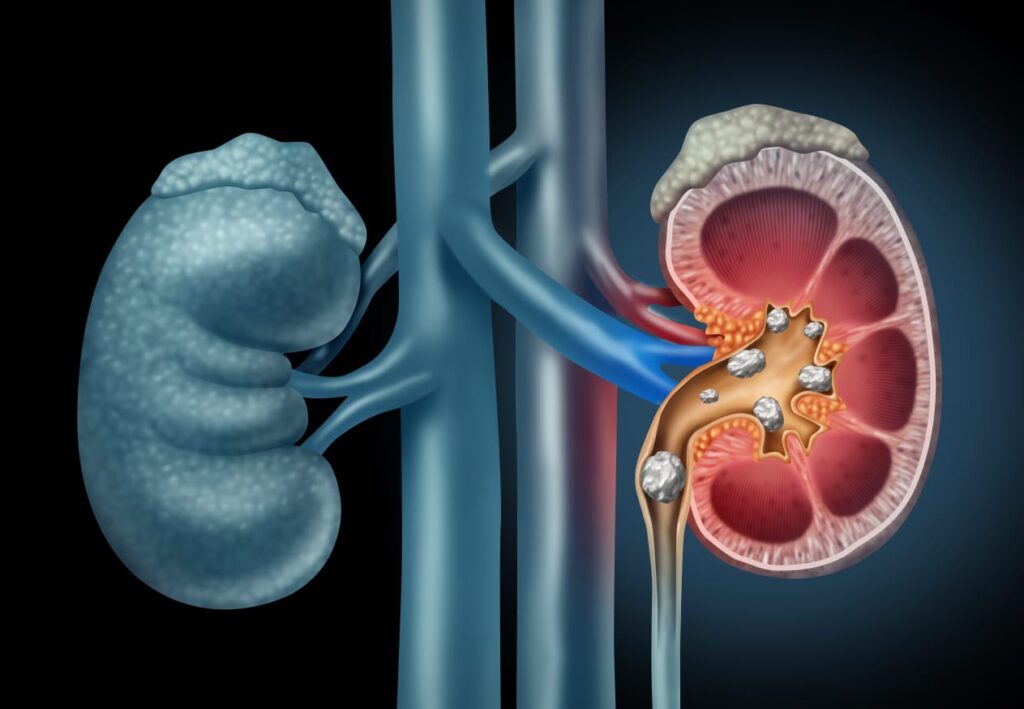

Jagrat Times, कानपुर : जीवन में व्यस्तता के कारण अक्सर लोग खानपान में गड़बड़ी कर देते है। नियमित संतुलित भोजन नहीं करना, एक्सरसाइज व योग न करना, सुबह नहीं टहलने के अलावा प्रदूषण के कारण भी अक्सर किसी न किसी बीमारी से ग्रसित हो जाते हैं। ऐसी ही आम बीमारियों में से एक है स्टोन या पथरी होना। यदि किसी को भी स्टोन यानी पथरी की शिकायत हो जाती है तो बिल्कुल भी घबराने की जरूरत नहीं है। इसका होम्योपैथिक विधा में कारगर और सफल इलाज है। और आपको कही भटकने की भी जरूरत नहीं है क्योंकि कानपुर व आसपास जिलों में मशहूर सीनियर होम्योपैथिक फिजिशियन डॉक्टर मधुलिका शुक्ला अपने अद्भुत इलाज के तरीके से इस बीमारी को जड़ से खत्म करने के लिए चर्चित है। स्टोन यानी पथरी के विषय में विस्तार से चर्चा करते हुए डाॅक्टर मधुलिका शुक्ला ने बताया कि मेरे पास सितंबर के महीने में राजन मिश्रा आए थे जिनकी किडनी में 35 मिमी की पथरी थी।

डॉक्टर मधुलिका शुक्ला ने बताया कि स्टोन यानी पथरी शरीर के अंदर बनने वाले कठोर, पत्थर जैसे जमाव होते हैं, जो किडनी, पित्ताशय, लार ग्रंथियों या अन्य अंगों में बन सकते हैं, और खनिजों और लवणों के जमने से बनते हैं। गुर्दे की पथरी सबसे आम है, जो मूत्र में कैल्शियम, ऑक्सालेट और यूरिक एसिड जैसे तत्वों से बनती है और छोटे होने पर पेशाब के साथ निकल सकती है, लेकिन बड़े होने पर तेज दर्द और अन्य समस्याएं पैदा कर सकती है, जिसके इलाज के लिए पानी पीना, आहार बदलना या सर्जरी की जरूरत पड़ सकती है। पथरी एक ठोस, क्रिस्टल जैसा पदार्थ है जो शरीर के विभिन्न हिस्सों में बन सकता है, खासकर किडनी में। यह तब बनती है जब मूत्र या पित्त में कुछ रसायन (जैसे कैल्शियम, ऑक्सालेट, यूरिक एसिड) बहुत ज्यादा हो जाते हैं और क्रिस्टल के रूप में जमने लगते हैं।

डॉक्टर मधुलिका शुक्ला ने पथरी या स्टोन के होने कारणों पर चर्चा करते हुए बताया कि कैल्शियम स्टोन सबसे आम, कैल्शियम ऑक्सालेट या कैल्शियम फॉस्फेट से बनते हैं। यूरिक एसिड स्टोन ज्यादा प्रोटीन खाने या गाउट होने पर बनते हैं। स्ट्रुवाइट स्टोन मूत्र मार्ग के संक्रमण के कारण बनते हैं।सिस्टीन स्टोन दुर्लभ, आनुवंशिक स्थिति के कारण बनते हैं। इस बीमारी के लक्षणों पर भी डाॅक्टर मधुलिका शुक्ला ने प्रकाश डालते हुए कहा कि पेट, कमर या साइड में तेज दर्द (पेशाब नली में पथरी खिसकने पर)। पेशाब करते समय जलन या दर्द। बार-बार पेशाब आना या पेशाब रुक-रुक कर आना। पेशाब में खून आना (रंग गहरा या लाल)। मतली और उल्टी, ठंड लगना और बुखार (संक्रमण होने पर), पर्याप्त पानी न पीना, ज़्यादा नमक, चीनी और एनिमल प्रोटीन (मांस, अंडे) खाना। मोटापा, पारिवारिक इतिहास और कुछ बीमारियां (जैसे क्रोहन रोग, गाउट) के कारण यह बीमारी हो सकती है।